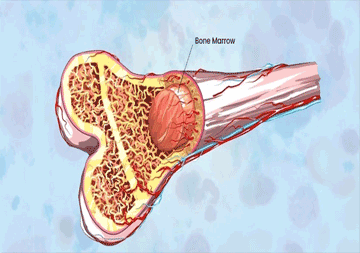

A well-recognized Pediatric Medical oncologist and hematologist practicing in New Delhi. In my career of 20 years in this field of pediatric Medical oncology and hematology, I have treated all kinds of hematological and solid cancers and have a keen interest in neuro-oncology. I have done more than 150 bone marrow transplant in last 8 years for both non- malignant and malignant conditions like thalassemia, aplastic anemia,, metabolic disorders, leukemias, lymphomas, Ewing’s sarcoma, brain tumors, neuroblastoma etc.